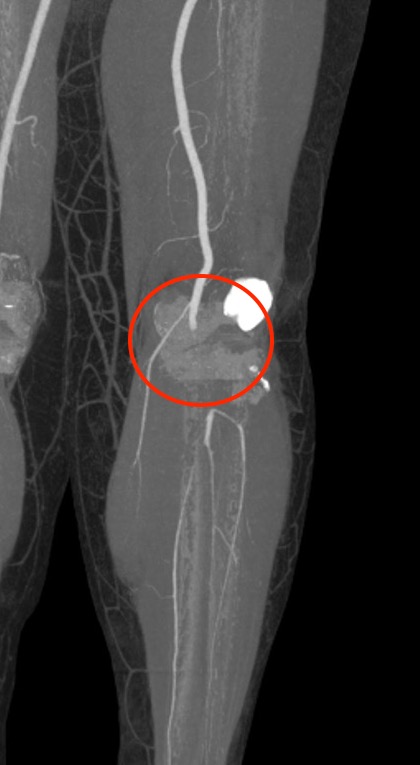

Normal CT angiogram Popliteal artery stenosis following knee dislocation

Popliteal artery transection following left knee dislocation

Advantages

- readily available, non invasive

- extremely accurate

- also used confirm the site and mechanism of injury

- multi-detector CT

- 100% sensitive and specific in detecting clinically significant arterial injury

Gakhal et al. Vascular and Interventional Radiology 2009

- CTA signs of lower extremity vascular trauma